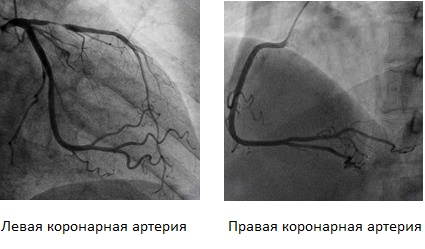

Анатомия коронарных артерий: КТ-изображения